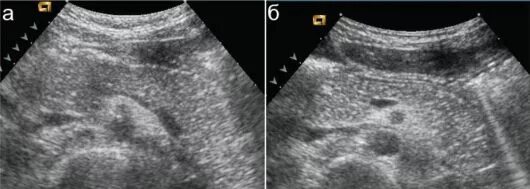

Диффузные изменения печени липоматоза